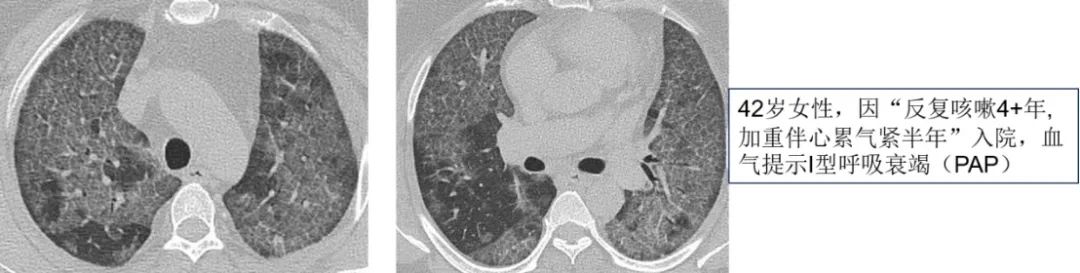

第三步,结合患者病史特征。虽然影像学特征能够提供鉴别方向,但单独影像学很难具体诊断某种疾病,因此需结合患者病史特征,包括详细的问诊及查体等。首先,我们需考虑疾病起病缓急,以双肺GGO为主要表现急性起病的疾病包括肺水肿、肺出血、PCP、支原体肺炎、病毒性肺炎、急性间质性肺炎、急性嗜酸性粒细胞肺病、早期过敏性肺炎、药物反应、淋巴瘤等;而慢性起病的疾病包括过敏性肺炎、DIP、RB-ILD、细胞性非特异性间质性肺炎、肺泡蛋白沉积症、细支气管肺泡癌(原位腺癌)、机化性肺炎、结节病。以图2病例为例,患者因重度Ⅰ型呼吸衰竭就诊,双肺表现为铺路石征及地图样改变,如果急性起病,我们可能首先会考虑PCP等可能,而患者4年缓慢进展的病史提示肺泡蛋白沉积症等慢性进展性疾病的可能性更大,而最终的肺泡灌洗液病理证实肺泡蛋白沉积症。

图2